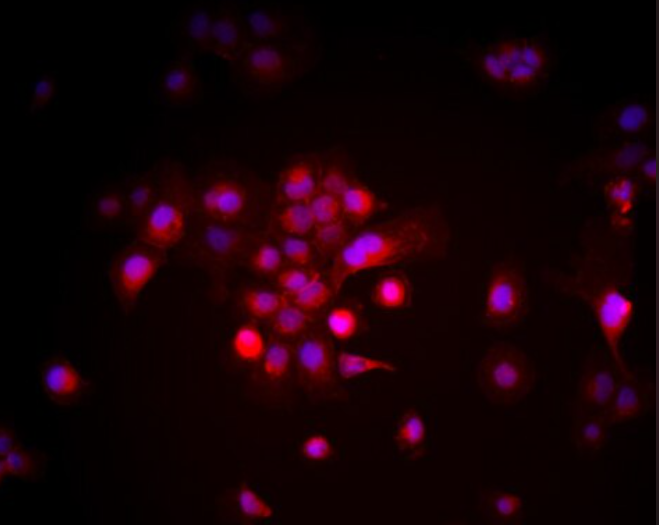

人胰腺癌细胞Capan-2Human Pancreatic Cancer Cell Line Capan-2

细胞来源

人胰腺腺癌原发灶(ATCC编号HTB-80

细胞类型

腺癌细胞

生长方式

贴壁生长,形态为上皮样细胞

人胰腺癌细胞Capan-2来源于一位患者的胰腺腺癌原发灶,是与Capan-1同属的经典腺癌细胞系之一,收录于ATCC(HTB-80)。Capan-2表现为规则贴壁生长,细胞形态为典型上皮样,具有良好的单层生长能力与较高的分化特征。该细胞表达CA19-9、MUC1、CEA、EGFR等常见胰腺癌相关标志物,同时携带KRAS和TP53突变。与Capan-1相比,Capan-2更具上皮特性,适合用于胰腺癌分子机制研究、信号通路激活分析、药物敏感性测试等实验。